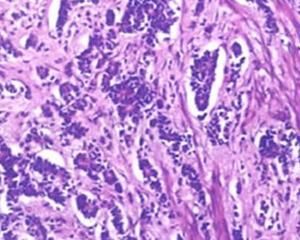

NSE在小細胞肺癌診斷中的意義

肺癌:NSE可作為檢測小細胞肺癌首選標誌物, 而CYFRA 21-1在非小細胞肺癌檢測中優於NSE。

60-81%小細胞肺癌病例NSE濃度升高。儘管NSE濃度與轉移部位或腦部轉移沒有相關性,但是與臨床分期如疾病進展有很好的相關性。